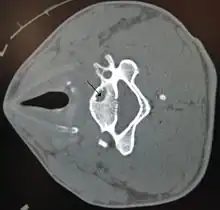

| A bone cyst in the vertebra of the neck as seen on CT | |

On CT scans, bone cysts that have a radiodensity of 20 Hounsfield units (HU) or less, and are osteolytic, tend to be aneurysmal bone cysts.[1]